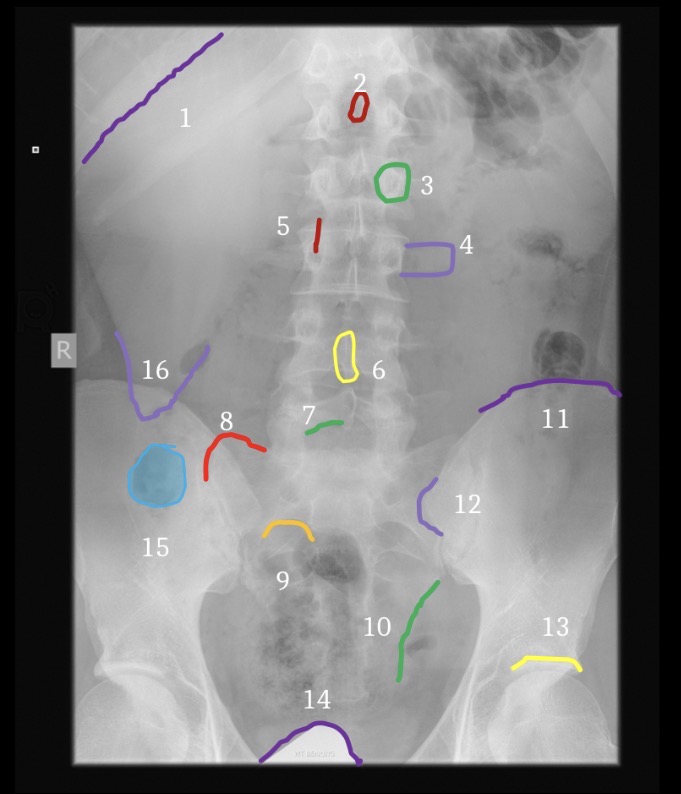

1

T12-L1 intervertebral foramen

2

Rib 12

3

Inferior articular process L2

6

Greater sciatic notch

5

Sacral canal

8

Sacral promontory

9

Iliac crest (2)

11

Transverse process L4

10

Superior articular process L5

12

Anterior body margin of L4

14

Anteriorsuperior body corner L3

15

Intervertebral disc space L1-2